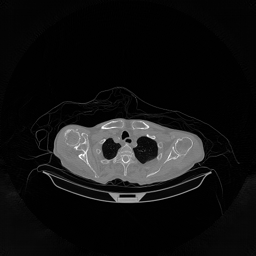

III-D Real Clinical Data Experiment

The experimental results on clinical head data are shown in Fig. 4. The reference images were reconstructed using the fast iterative shrinkage-thresholding algorithm (FISTA) with total variation regularization from non-truncated projection data. In the WCE reconstructions (Fig. 4(b)), severe truncation prevents accurate recovery of anatomical structures outside the FOV. Despite being trained solely on simulated data with a domain gap, all deep learning models can restore a substantial portion of the missing anatomy. Among them, the diffusion-based methods recover soft-tissue boundaries more faithfully than the conventional deep learning approach FBPConvNet, highlighting their stronger image generation capability. However, cDDPM reconstructions exhibit more noticeable noise than those from other methods, consistent with the simulated data results. The patchDiffusion model introduces artifacts within the FOV, likely due to its patch-wise processing strategy. While I2SB shares the same limitations as other diffusion models in perfectly restoring soft-tissue detail, it produces fewer residual noise patterns and fewer artifacts within the FOV boundaries. Overall, Fig. 4 demonstrates the strong efficacy of I2SB in reconstructing real CBCT data.

We validated I2SB and other diffusion models on both simulated noisy data and real head CBCT data. For the real data, the most prominent errors occurred in the soft tissues near the head boundary. This is primarily because the WCE method assumes that missing projection data corresponds to soft-tissue (water-equivalent) attenuation, making it challenging for deep learning models to accurately estimate the true boundary. In addition, the training data were simulated from the CQ500 dataset using the same C-arm CBCT system, introducing an inevitable domain gap between simulated training data and real test data. Future work will focus on acquiring more real CBCT data to train I2SB, which is expected to further improve reconstruction quality and generalization performance.